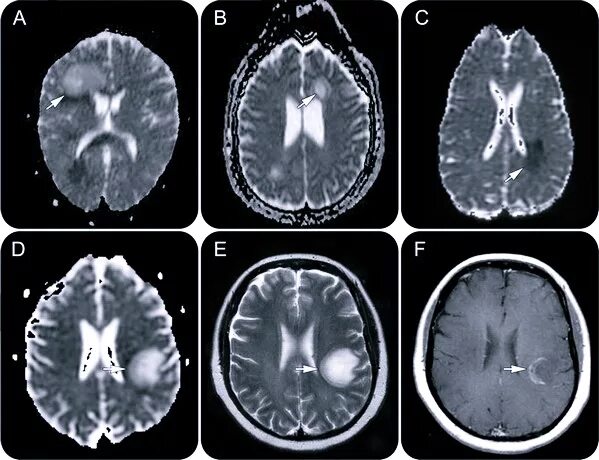

Белые очаги в головном мозге